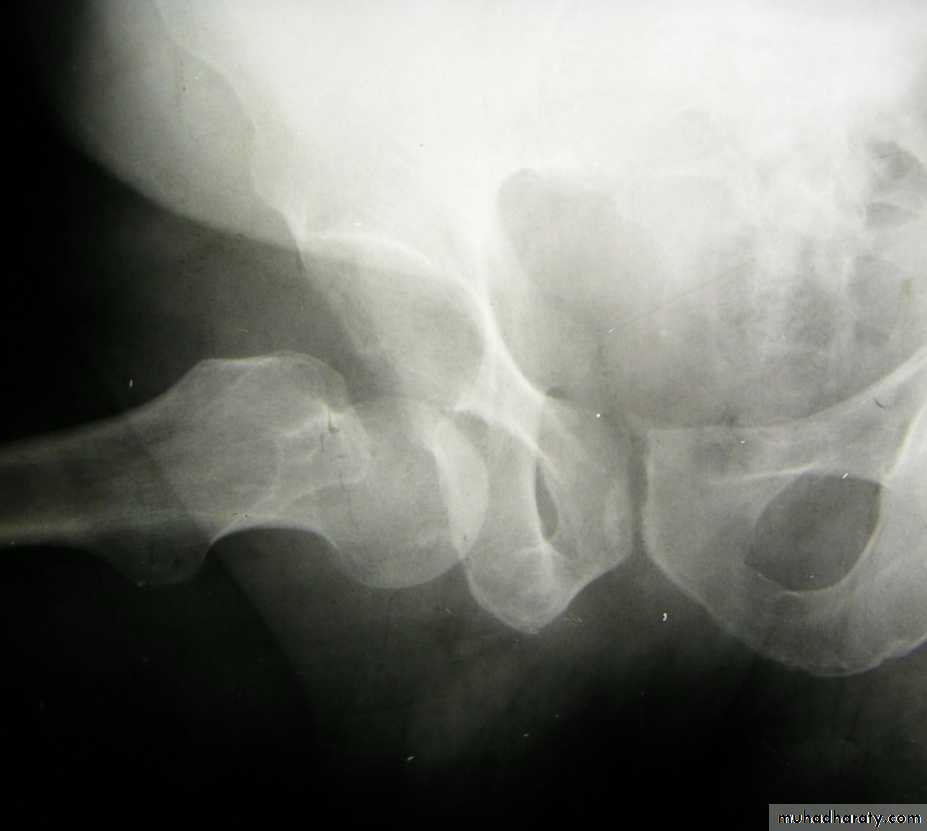

Central fracture -dislocation

Lower limbs